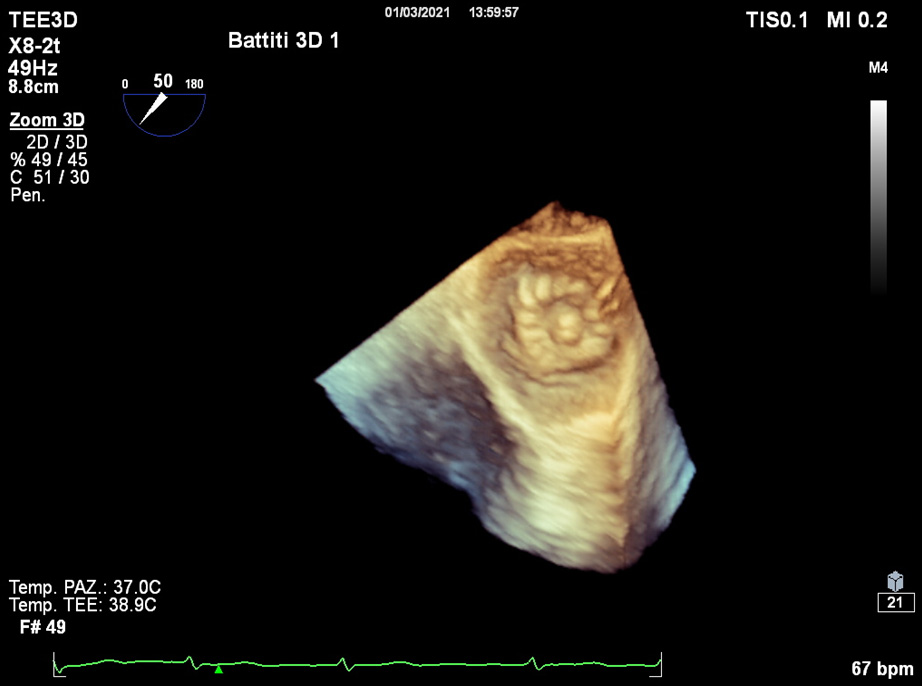

Although 2D TOE represents the routinely modality for pre-operative assessment, the use of 3D TOE gives practical additive information in identifying uncommon morphologies [12], and its use is increasing. While its anatomic estimations are superior to 2D TOE, slow temporal resolution of 3D TOE and lacking professional guidelines still represent limitations of this technique.

Detailed characterization of the LAA body and orifice shapes can facilitate device selection (Fig. 5).

Fig. 5.The use of 3D TOE provides useful additive evaluation about unusual morphology or irregular orifices.